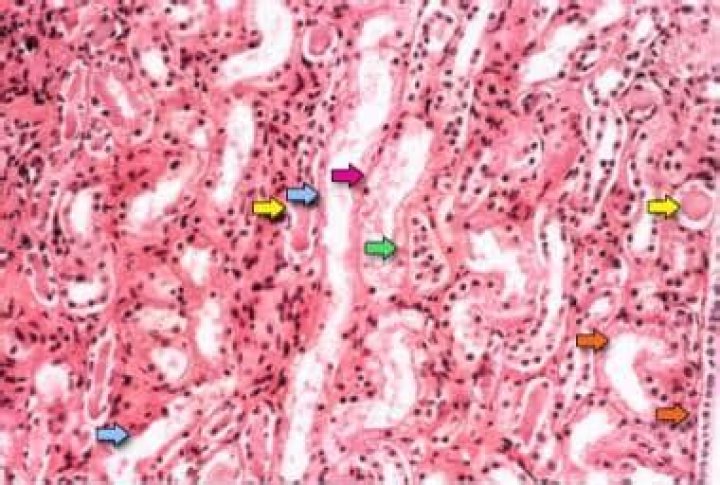

Acute tubular necrosis is kidney injury caused by damage to the kidney tubule cells (kidney cells that reabsorb fluid and minerals from urine as it forms). Common causes are low blood flow to the kidneys (such as caused by low blood pressure), drugs that damage the kidneys, and severe bodywide infections.